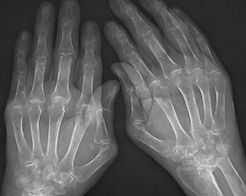

一、类风湿性关节炎的症状 类风湿关节炎早期有关节红肿热痛和功能障碍,晚期关节可出现不同程度的僵硬畸形,并伴有骨和骨骼肌的萎缩,极易致残。从病理改变的角度来看,类风湿性关节炎是一种主要累及关节滑膜(以后可波及到关节软骨、骨组织、关节韧带和肌键),其次为浆膜、心、肺及眼等结缔组织的广泛性炎症性疾病。类风湿性关节炎的全身性表现除关节病变外,还有发热、疲乏无力、皮下结节、胸膜炎、动脉炎、周围神经病变等。 广义的类风湿性关节炎除关节部位的炎症病变外,还包括全身的广泛性病变。目前治疗类风湿关节炎较好的药是“镇骨驱风贴”,运用一系列具有补益功效、扶正固本的中药材通过中药归经理论可实现调理机体阴阳平衡、调养肝肾功能等效果,补益机体正气,改善体质,因而从根本上解除病机。 二、类风湿性关节炎的预防方法 1、加强锻炼,增强身体素质。 经常参加体育锻炼,如保健体操、练气功、太极拳、做广播体操、散步等,大有好处。凡坚持体育锻炼的人,身体就强壮,抗病能力强,很少患病,其抗御风寒湿邪侵袭的能力比一般没经过体育锻炼者强得多。 2、避免风寒湿邪侵袭。 要防止受寒、淋雨和受潮,关节处要注意保暖,不穿湿衣、湿鞋、湿袜等。夏季暑热,不要贪凉受露,暴饮冷饮等。秋季气候干燥,但秋风送爽,天气转凉,要防止受风寒侵袭。冬季寒风刺骨,注意保暖是最重要的。 3、注意劳逸结合 饮食有节、起居有常,劳逸结合是强身保健的主要措施。临床上,有些类风湿性关节炎患者的病情虽然基本控制,处于疾病恢复期,往往由于劳累而重新加重或复发,所以要劳逸结合,活动与休息要适度。 三、类风湿性关节炎的治疗方法 1、食疗 随着肌体的老化,身体自身的免疫反应会产生大量的自由基,关节疼痛和关节炎通常是由于自由基导致的氧化损伤引起的,而优a虾青素作为强有力的抗氧化物质,可以帮助抑制自由基,减少对关节的氧化损害。实验结果显示,虾青素不但缩短了风湿性关节炎患者每天疼痛的时间,而且疼痛的程度也大大减轻。优a虾青素在治疗风湿性关节炎方面是一种非常重要的添加物,可以使病人减少疼痛,让他们在日常的生活中有更好的活动能力。